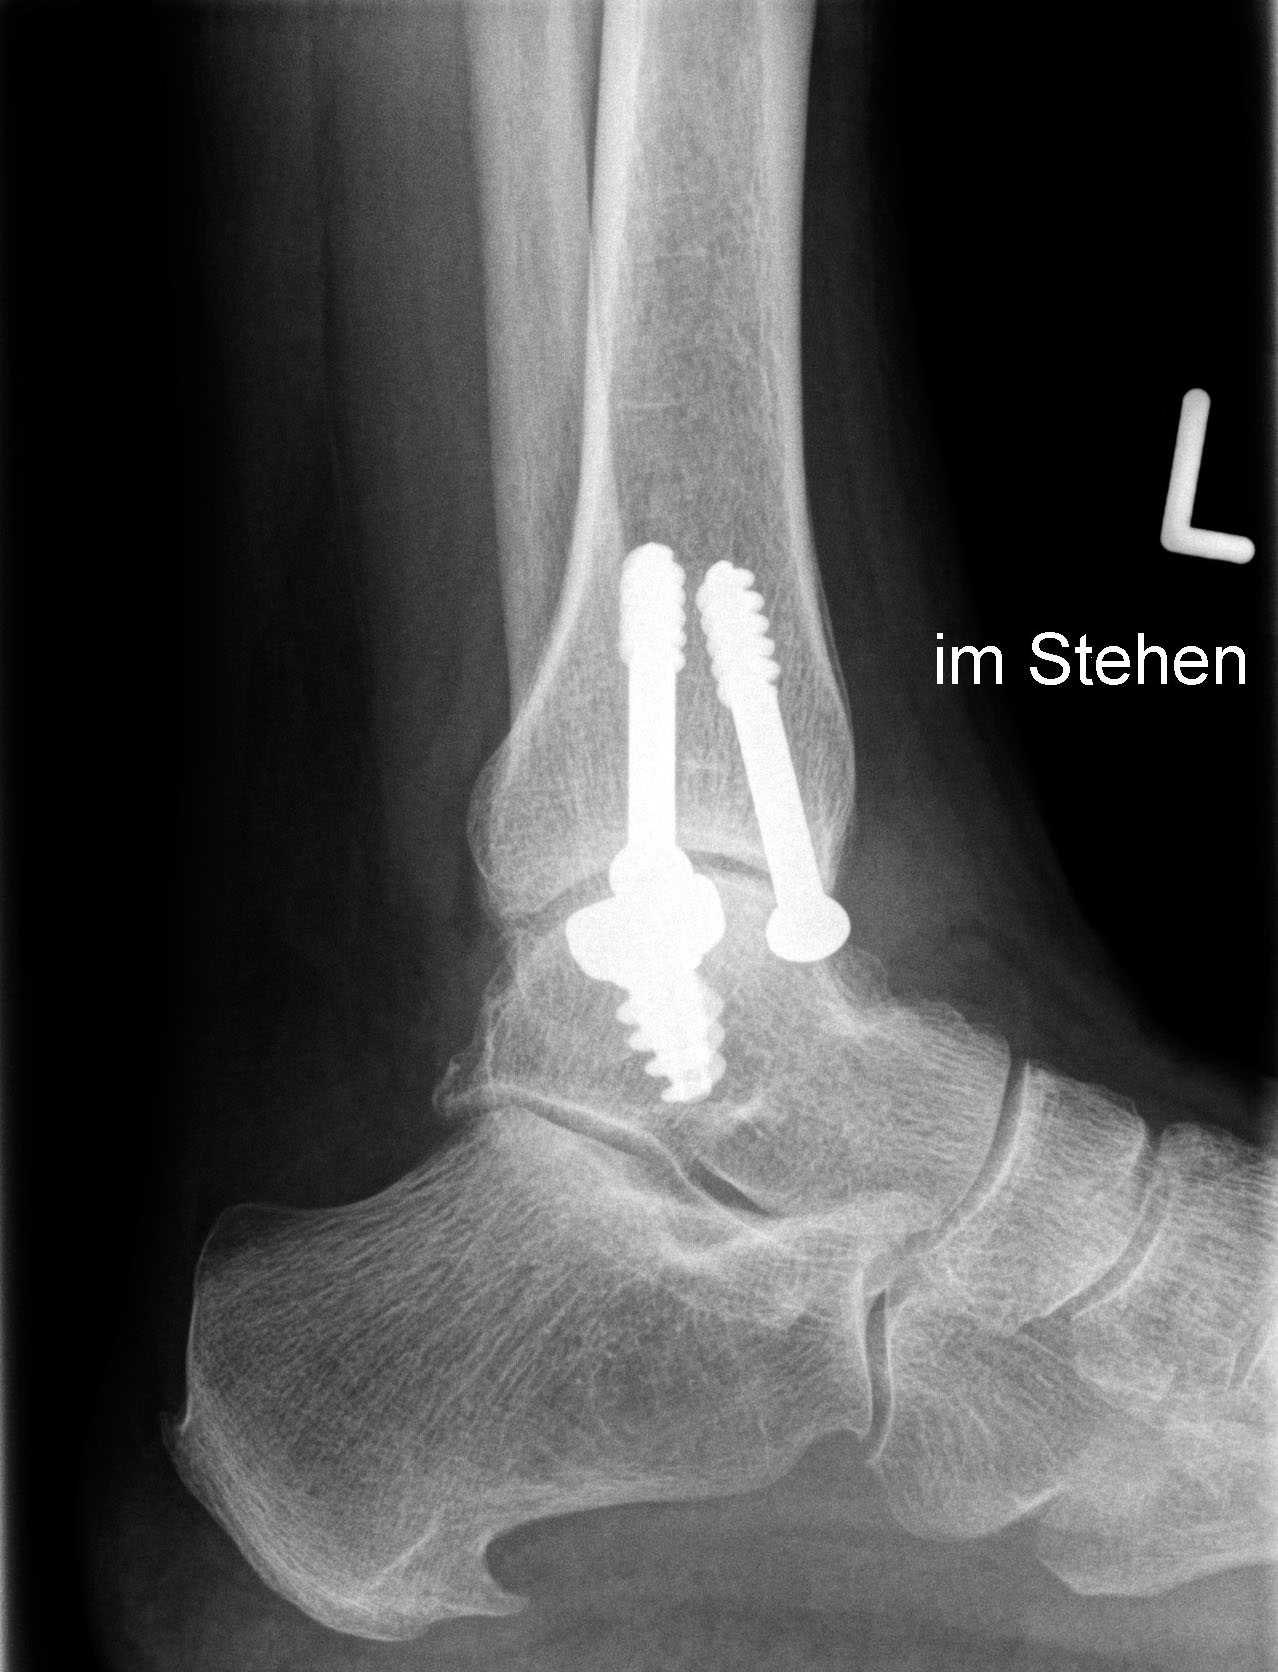

Eine vorausgehende Arthroskopie ist zu empfehlen. Zum Einbringen des Implantates ist eine Osteotomie des medialen Malleolus erforderlich.

Zum Lesen der Bildbeschreibung und zur Vollansicht bitte die Bilder anklicken. Bilder: Christoph Becher.

Abschließend erfolgt die Osteosynthese des medialen Malleolus und der schichtweise Wundverschluss. Anschließend Anlegen eines sterilen Wundverbandes sowie Ruhigstellung in einer Gipslonguette in Neutralstellung.

CAVE: Bei der postoperativen Röntgenkontrolle muss bedacht werden, dass die Knorpelschicht nicht abgebildet ist. Da das Implantat bei einer korrekten Positionierung unterhalb des Knorpelniveaus die knöcherne Fläche dennoch etwas überragt, kann dies zu einer Fehlinterpretation führen, dass das Implantat übersteht.

Zum Lesen der Bildbeschreibung und zur Vollansicht bitte die Bilder anklicken. Bilder: Sarah Ettinger.